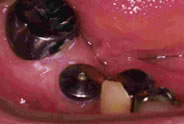

上の奥歯を抜歯しました。抜歯した部分の骨が無くなりくぼんでいます。

CTで調べるとインプラントを埋入する骨の量が足りません。 歯肉側の骨も失われていることがわかります。

歯肉側にはGBR法、上顎洞底部はソッケトリフトを併用して足りない骨を作ります

インプラント体が3本入りました